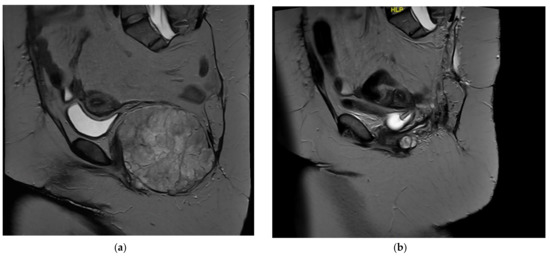

4. Case Presentation